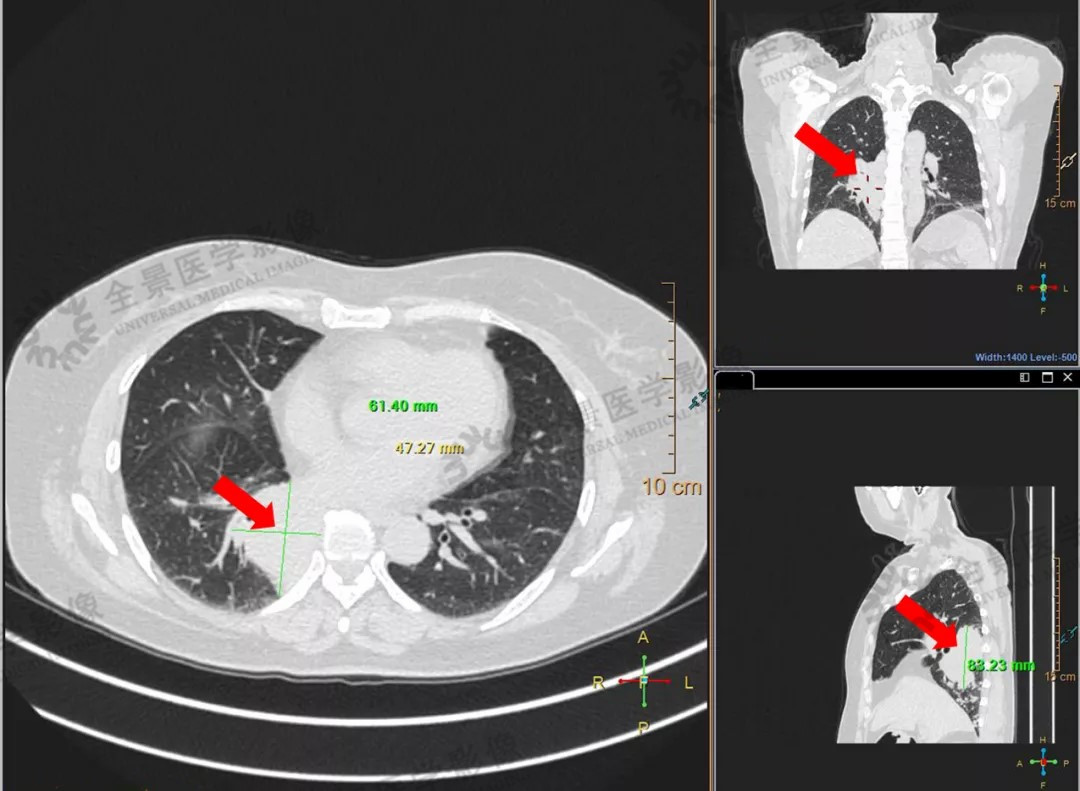

中年女性,咳嗽半年,做CT检查发现有占位性病变,但不能确定性质。通过PET/CT,发现右肺下叶肿块,在双侧肺门淋巴结、左侧股骨颈、脑部等多部位有代谢异常增高区域,考虑多处转移。

右肺下叶软组织肿块

左股骨颈骨质破坏